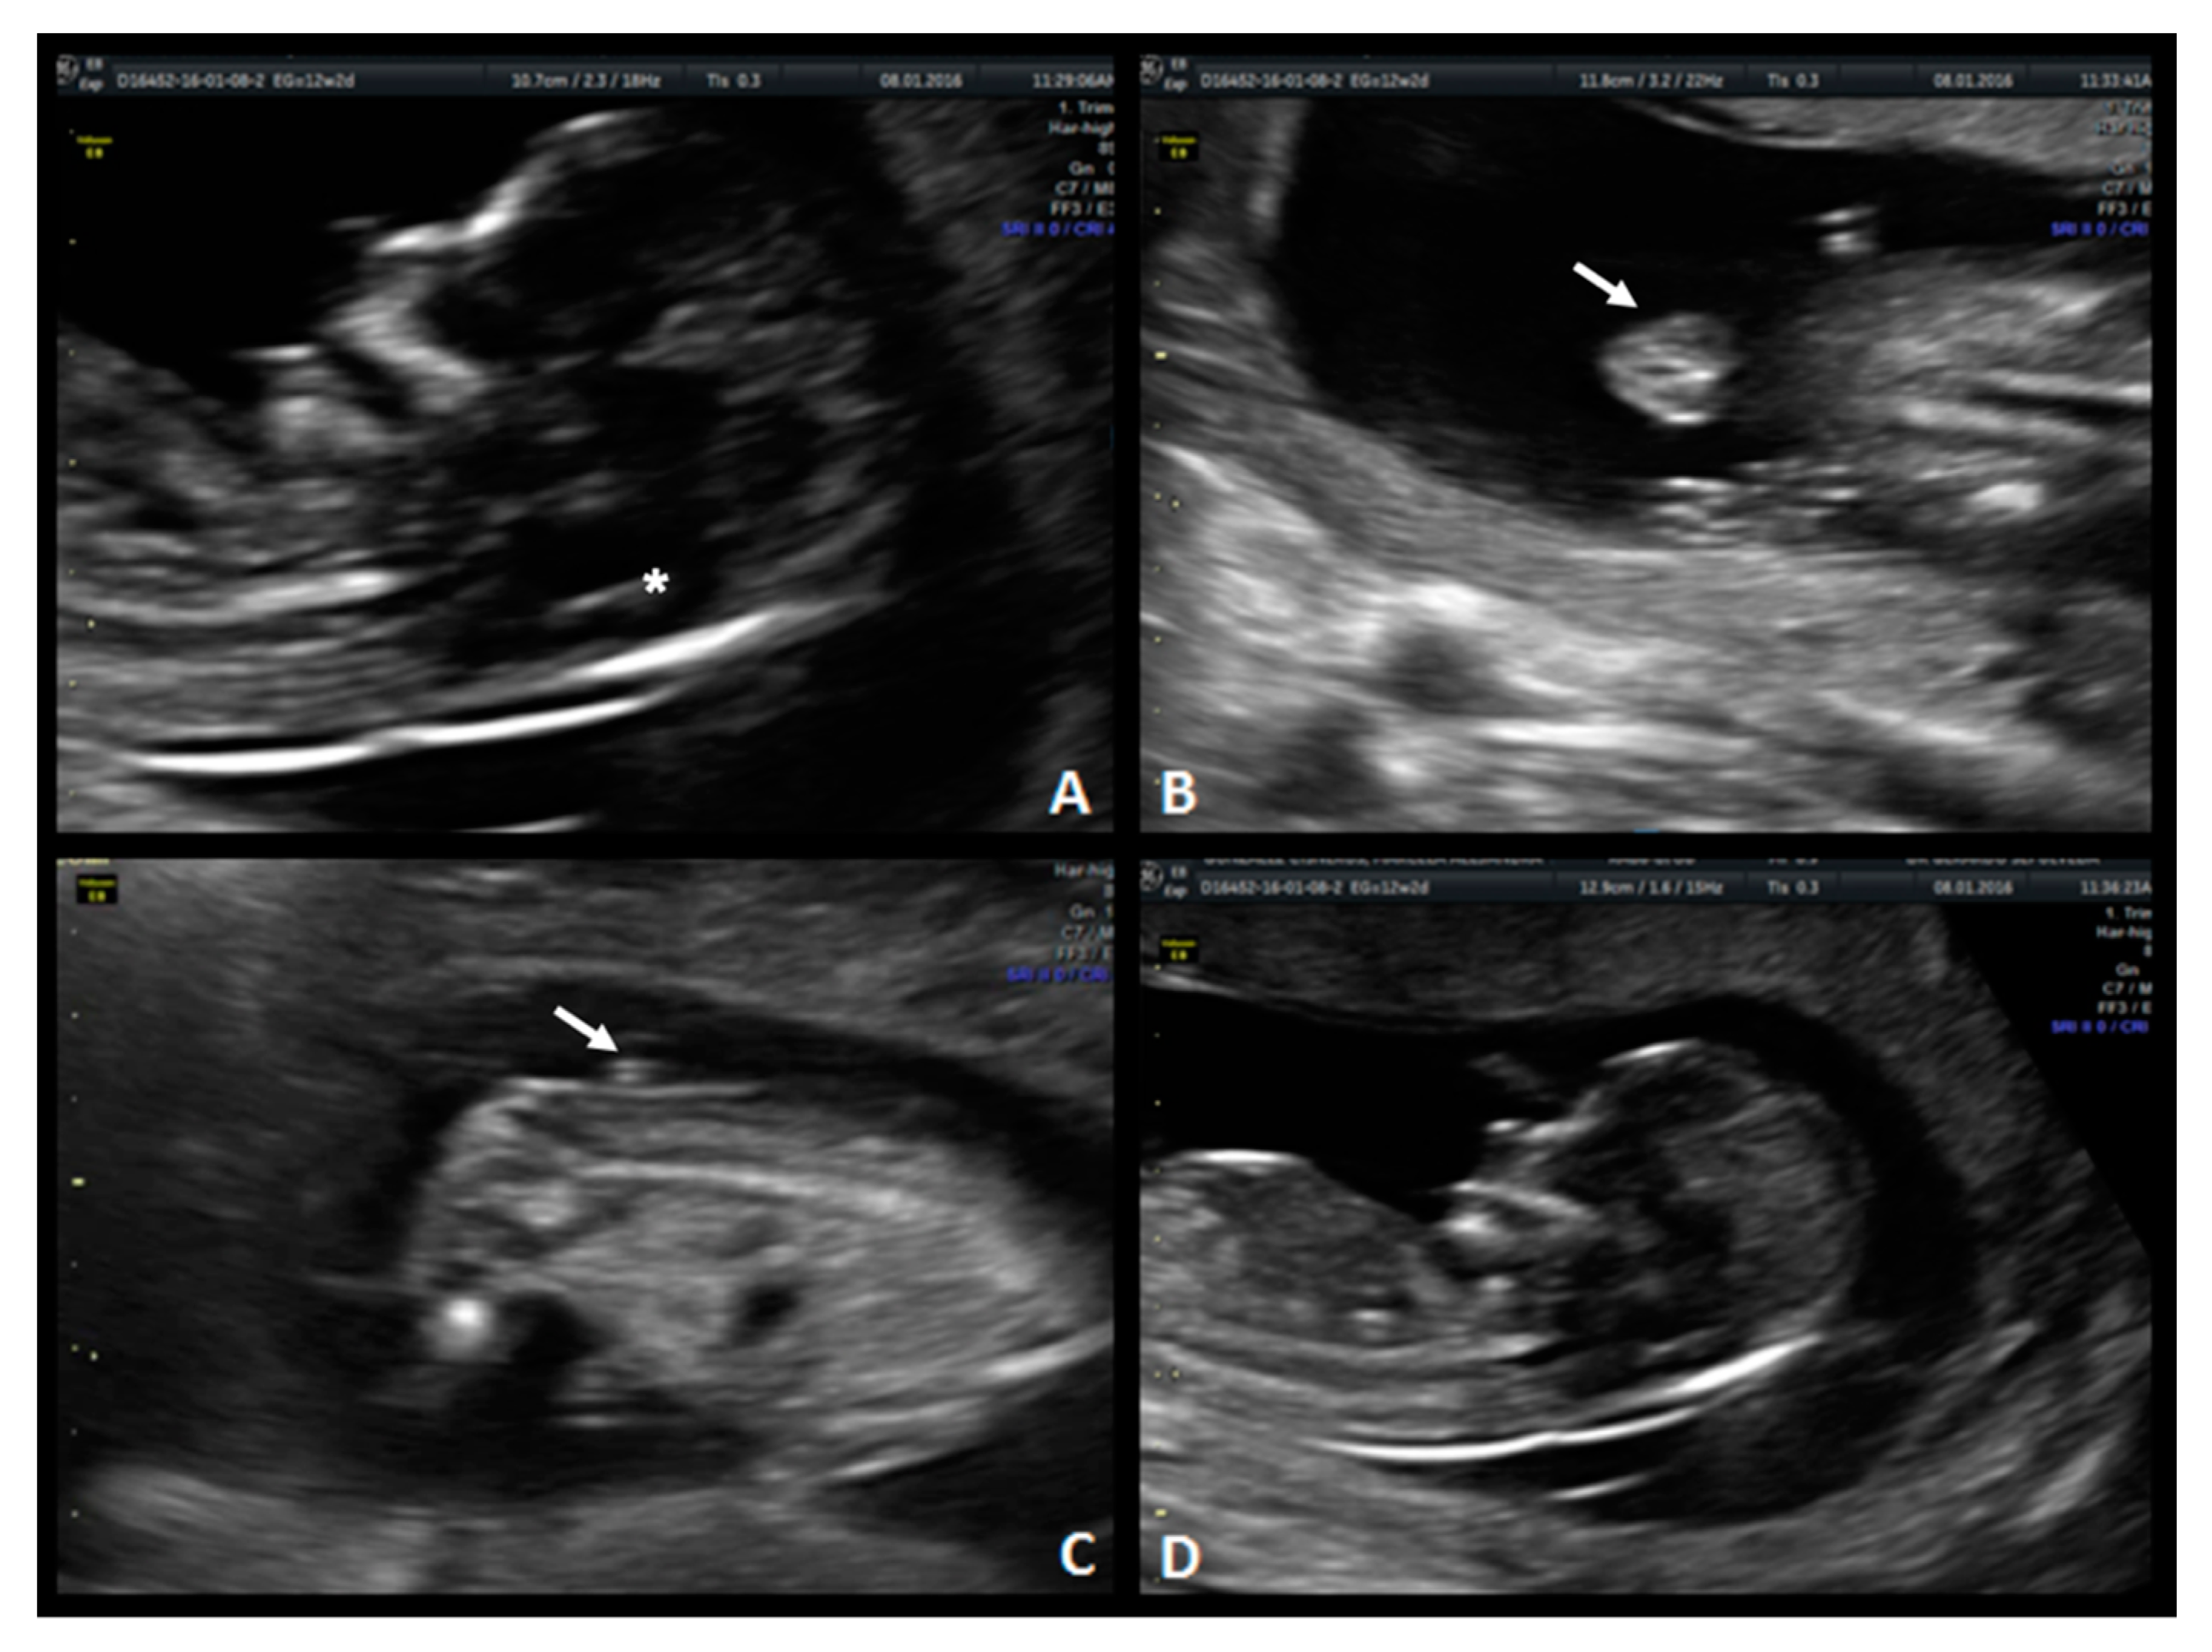

A 31-year-old, G1 healthy woman was referred for first-trimester screening at 13.1 weeks of gestation. The fetus had a CRL of 76.0 mm, NT was 1.4 mm, the nasal bone was present, and the IT absent. Diagnosis of spina bifida was suspected, and she was classified as a high-risk patient. The US scan at 18 weeks of gestation showed the typical “lemon” and “banana” signs. A lumbosacral SBA was observed (Figure 4). After counseling, this patient opted for fetal surgical repair.

Figure 4. Case 3. First-trimester scan: (A) mid-sagittal plane of the fetal face demonstrates compression of the fourth ventricle with no visible IT (white arrow). (B) Sagittal view of the lower back with a lumbar spine defect (white arrow) (C) axial plane of the spine shows the myelomeningocele (white arrows) (D) Axial image.